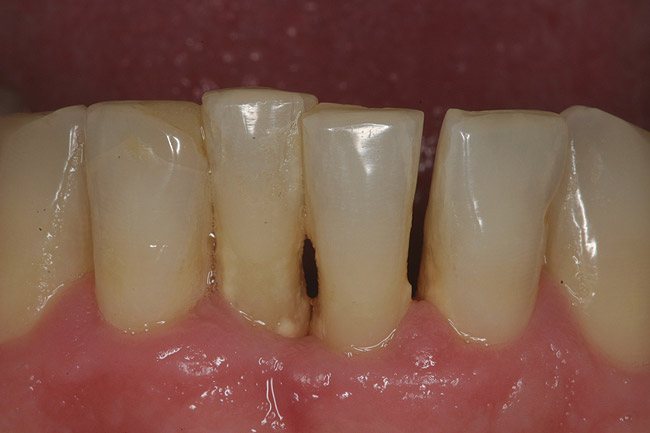

Figure 1  The preoperative clinical condition.

Figure 1

A 53-year-old man presented with localized advanced periodontal disease of the mandibular incisors. Teeth Nos. 23 to 26 exhibited class II mobility because of advanced bone loss (Figure 1). The teeth had migrated out of position over the years, and a diastema had developed between teeth Nos. 24 and 25 (Figure 2). The patient complained about the poor esthetic appearance of these teeth, and he was able to perceive their loss of strength on function as a result of their mobility.